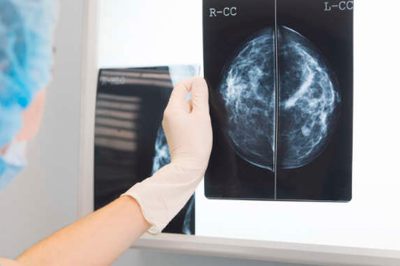

Os tipos de câncer que mais levam a mortes devem ser os de pulmão (18,4%), reto (9,2%) e estômago (8,2%). Já nos novos casos, as modalidades com maior incidência devem ser as de pulmão (11,6%), mama (11,6%) e reto (10,2%). Juntos, estas representam cerca de um terço dos registros da doença em todo o mundo.

No recorte por gênero, entre os homens os tipos de câncer mais comuns devem ser os de pulmão (14,5% do total), próstata (13,5%) e reto (10,9%). Já entre as mulheres, as modalidades com maior incidência devem ser câncer de mama (24,2%), seguido por de reto e de pulmão. Nos dois gêneros, o câncer de pulmão deve fechar o ano como o principal responsável por mortes.